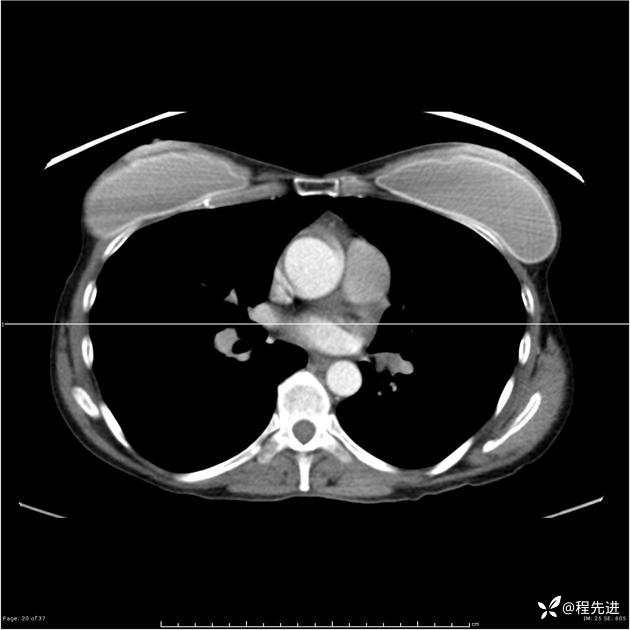

病例女,53岁,气管、左主支气管、下叶支气管内结节,乳头状瘤?期待你的精彩解读

女,53岁

乳头状瘤?